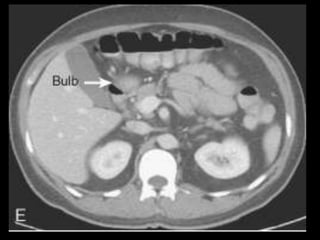

Pâncreas anular

Rara anomalia congênita

1 em cada 20.000 nascimentos

Caracteriza-se por uma parte de tecido

pancreático, em continuidade com a cabeça, que

circunscreve parcial ou totalmente o duodeno;

Circunda habitualmente a 2ª. porção(74%) e em

menor proporção a 1ª. (21%);

Associa-se comumente a anomalias duodenais

como atresia, estenose ou atrofia.

A CPER mostra um ducto pancreático aberrante

circundando o duodeno.

O local de drenagem desse ducto é variável;

A RM e a TCMD mostram tecido pancreático

circundando o duodeno, que conserva a densidade

e a intensidade de sinal do pâncreas normal

remanescente, tanto no exame basal como após a

administração de contraste.

Imagens T1 com supressão de gordura são úteis.

Diferenciação com neo pancreática ou duodenal.